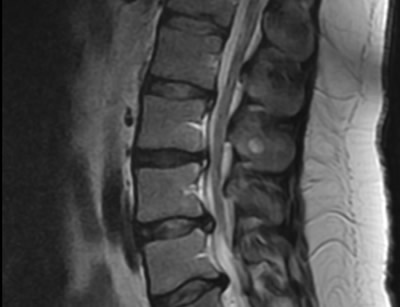

IMÁGENES

Galería de imágenes